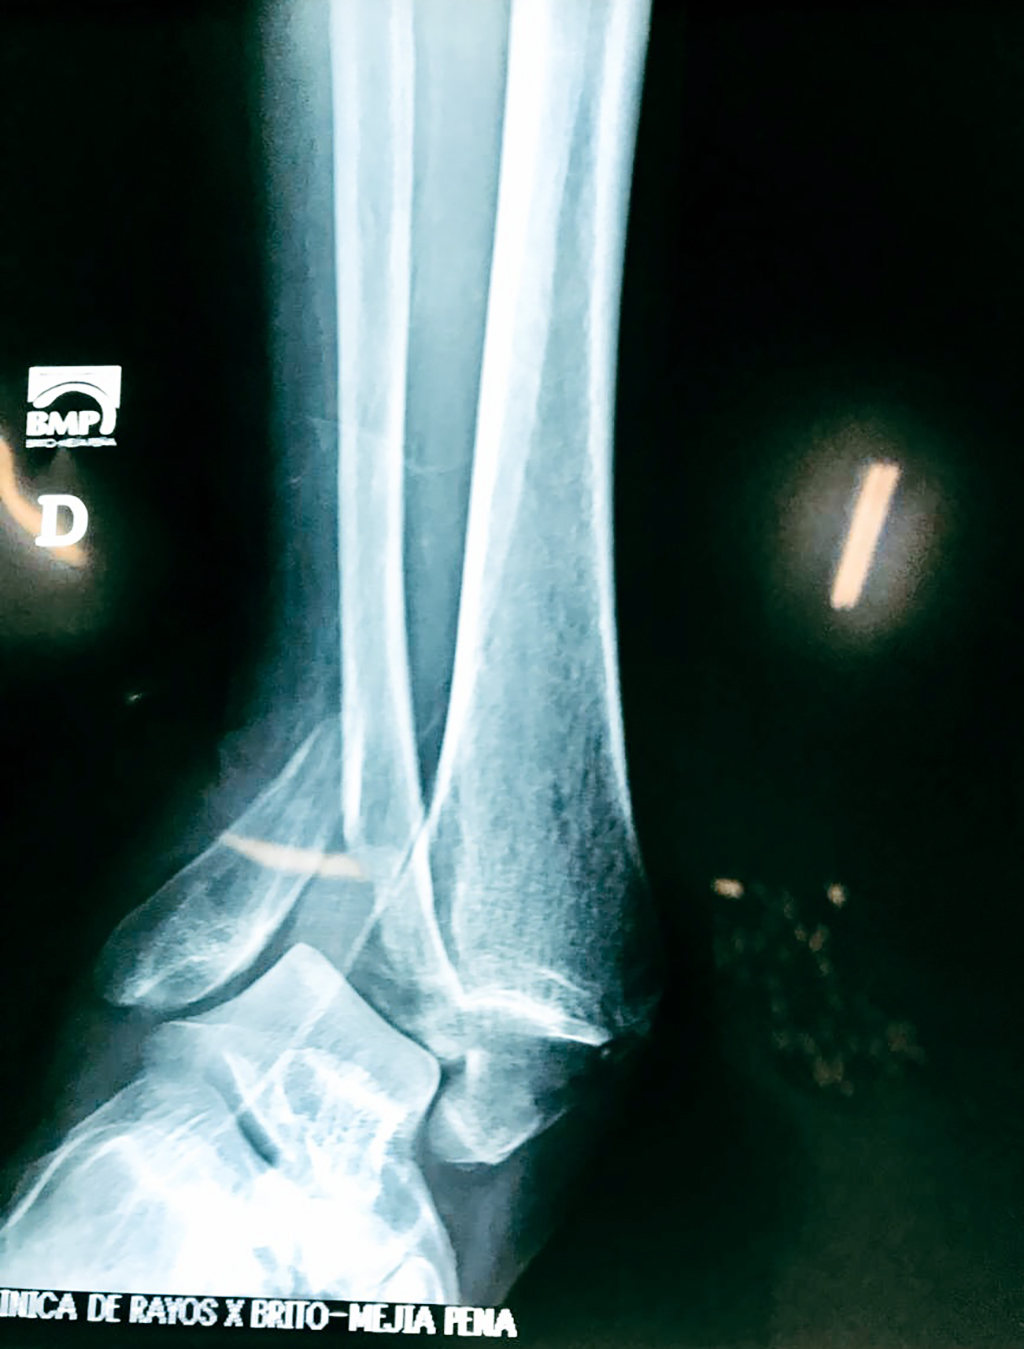

Una fractura de tobillo es la rotura de uno o más de los huesos del tobillo. Estas fracturas pueden ser:

Algunas fracturas de tobillo pueden requerir cirugía si:

- Los extremos de los huesos están desalineados entre sí (desplazados).

- La fractura se extiende hasta la articulación del tobillo (fractura intra-articular).

Cuando se necesita cirugía, es probable que esta implique el uso de clavijas de metal, tornillos o placas para sostener los huesos en su lugar mientras la fractura se consolida. Los elementos de soporte pueden ser temporales o permanentes.